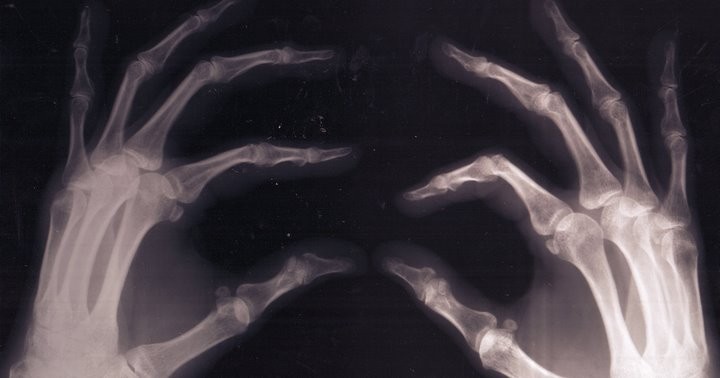

С возрастом или из-за неправильного образа жизни кости человека могут стать хрупкими, появляются серьезные проблемы со здоровьем. Если питаться несбалансированно, с частыми перекусами на ходу, возможен дефицит витаминов и минеральных веществ. В частности, опасна нехватка кальция и витамина D, ведь это своего рода строительный материал для костей.

Входящие в состав фастфуда или кондитерских изделий траснжиры могут привести к формированию патогенной микрофлоры и плохой усвояемости отвечающего за формирование костной ткани витамина К2.

— Если микрофлора нормальная, организмом лучше усваивается витамин К2, отвечающий за формирование костной ткани. Если этого витамина недостаточно или он плохо усваивается, это может вести к истощению костей, — сказал Ю. Костенко.

Негативно сказывается на состоянии костей также частое и бесконтрольное употребление соли, соленых продуктов, рассолов. Их нужно употреблять в умеренном количестве. Соль состоит в основном из хлорида натрия, а это антагонист кальция, соответственно, этого полезного вещества становится меньше.

Что касается напитков, то врач предостерег от чрезмерного потребления газировок, особенно сладких. В них содержится большое количество различных кислот, часто присутствует ортофосфорная. Если регулярно пить газировки, кальций может вымываться из костей, что делает их более хрупкими.